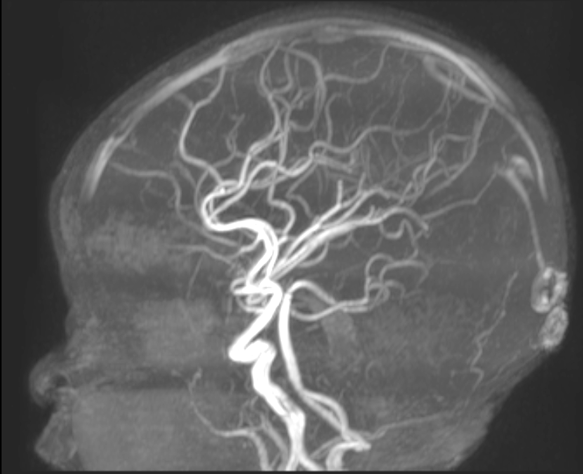

An MRI revealed that Maryam had hemimegalencephaly, a rare neurological condition where one half of the brain is enlarged and can cause epilepsy, developmental delays and muscle weakness. In this case, it had affected the left hemisphere of Maryam’s brain. She was immediately rushed to The Hospital for Sick Children (SickKids).

“Instead of traditional surgery, which would have required opening her skull and cutting connections in her brain, this approach allowed us to work through her blood vessels, minimizing risks and recovery time,” explains Dr. Prakash Muthusami, an interventional neuroradiologist at SickKids who led the eventual series of procedures and leads the hospital’s Neurointerventional Program.

As opposed to an open surgical procedure, the endovascular approach involves using catheters introduced inside blood vessels to selectively block blood flow to the abnormal areas of the brain, effectively “disconnecting” the problematic hemisphere while preserving healthy tissue.

The technique essentially targets dysfunctional areas of the brain, and by cutting the connection, protects the functioning half of the brain.

Between February and April 2024, four carefully planned embolization procedures, spaced two to three weeks apart, successfully isolated Maryam’s left hemisphere.

And at every step, the Interventional Neuroradiology team, Epilepsy and Neurosurgery teams worked together, using detailed electroencephalogram (EEG) and brain MRI scans to ensure precision and safety.